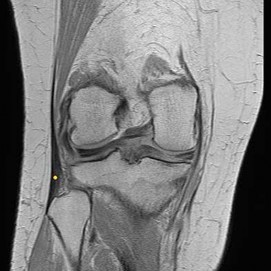

CLINICAL SITUATION FOR QUESTIONS 22 THROUGH 25

A 22-year-old man sustains an injury to his right knee in a motor vehicle collision. Figure 22a is the posterior stress radiograph of the involved knee, and Figure 22b is a selected MR image that identifies the injured structure.

Which relationship is noted for the structure identified by the arrow in Figure 22b? 24

- The anterolateral bundle is tensioned in mid flexion, and the posteromedial bundle is tensioned in both extension and high flexion.

The stress radiographs demonstrate posterior instability of the right knee in flexion. The MR images demonstrate injury to both the anterior and posterior cruciate ligament (PCL), with the stump identified with the arrow on the MR image (Figure 22b). The PCL has 2 functional bands. The anterolateral bundle originates from the roof of the intercondylar notch. It runs in a posterolateral direction onto the tibial crest between the posterior attachment of the medial and lateral menisci. During a double-bundled posterior ligament reconstruction, the

anterolateral bundle is tensioned with the knee in a position of mid flexion. The posteromedial bundle has a variable pattern of tension both in extension and in high flexion. Tensioning of the posteromedial bundle in extension may contribute to resistance against knee hyperextension.